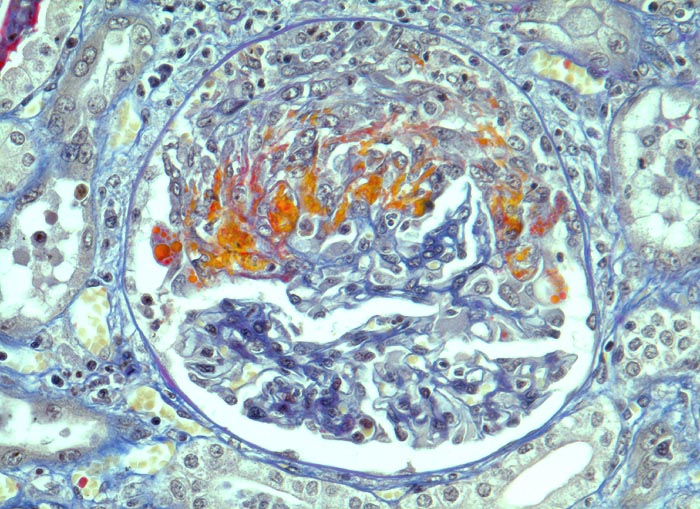

extrakapilläre Glomerulonephritis bei Morbus Wegener

Frische segmentale Schlingennekrosen mit exsudiertem Fibrin und Protein (rot). Beginnende Proliferation von Kapselzellen. Dazwischen einzelne neutrophile Granulozyten.

Rapid progressive Glomerulonephritis mit Entwicklung einer Oligurie innert weniger Tage. Fieber und Nachtschweiss. Chronische Sinusitis. cANCA erhöht.

Halbmondbildung: Sichelförmige Proliferation von Kapselepithelien als Antwort auf eine lokale Fibrinexsudation aus geschädigten/nekrotischen Glomeruluskapillaren.